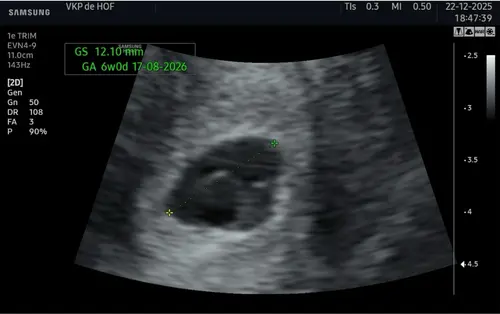

Omdat het gevoel bleef knagen, heb ik op 22 december een pretecho laten maken. Volgens mijn berekening zou ik toen 6 weken en 3 ( ? ) dagen zwanger zijn.

De verloskundige dacht op basis van de echo dat ik eerder rond de 6 weken zat (zie echo).

Er was toen nog geen kloppend hartje te zien. Daarom moesten we vandaag terugkomen voor een controle-echo.

Eerste echo is van 22 december andere echo van 31 december